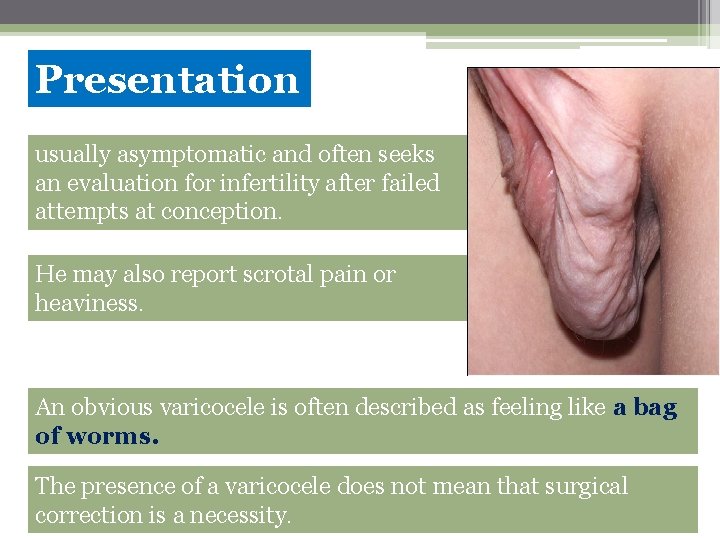

Presentation usually asymptomatic and often seeks an evaluation for infertility after failed attempts at conception. He may also report scrotal pain or heaviness. An obvious varicocele is often described as feeling like a bag of worms. The presence of a varicocele does not mean that surgical correction is a necessity.